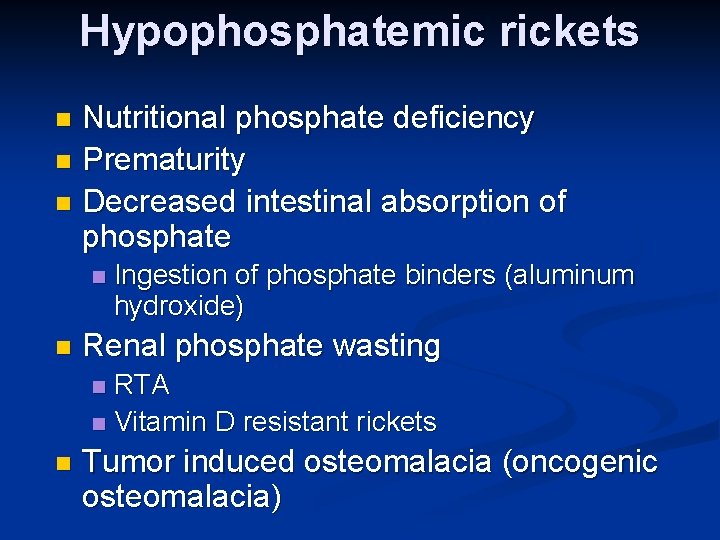

Hypophosphatemic rickets Nutritional phosphate deficiency n Prematurity n Decreased intestinal absorption of phosphate n n n Ingestion of phosphate binders (aluminum hydroxide) Renal phosphate wasting RTA n Vitamin D resistant rickets n n Tumor induced osteomalacia (oncogenic osteomalacia)